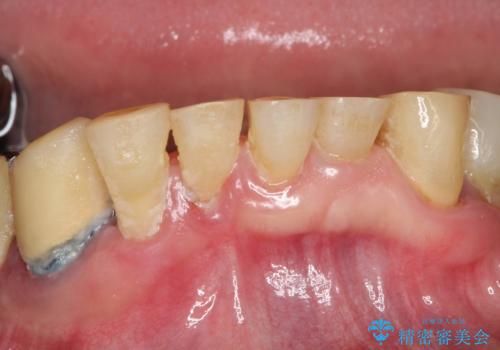

虫歯だらけ、歯周病 崩壊した口腔の再建 フルマウスリコンストラクション

- 歯周外科・インプラント・顕微鏡下根管治療などを含んだ総合的な治療を計画した。

様々な治療手段を高いレベルで同時に併行して行うことが必要でした。

かみ合わせの力が非常に強く、夜間の歯ぎしり・食いしばりもひどかったため、奥歯はメタルオクルーザルの設計でかぶせ物を製作しています。